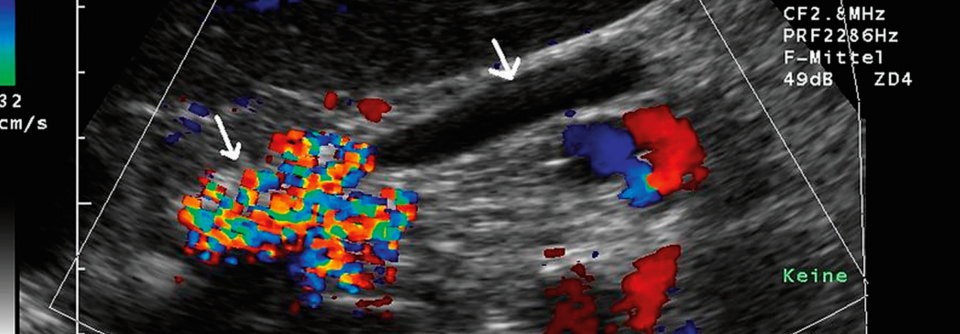

Bei einer 46-jährigen Frau wird eine akute Pankreatitis diagnostiziert. Die Patientin hat einen BMI von 35 und erhält wegen ihres erst kürzlich festgestellten Typ-2-Diabetes Metformin. Aufgrund von Wechseljahresbeschwerden wurde ihr zudem eine Hormonersatztherapie verschrieben, zur kardiovaskulären Primärprävention nimmt sie Statine. Zum Zeitpunkt der Pankreatitisdiagnose sind der Blutzucker mit 306 mg/dl und vor…